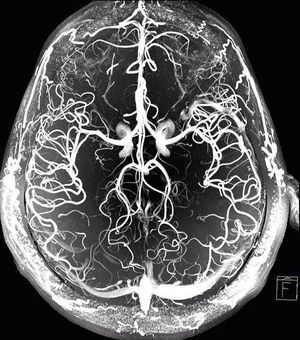

7.0 Tesla MRA of the brain!!!

Mri

Mra

Ultra High Field